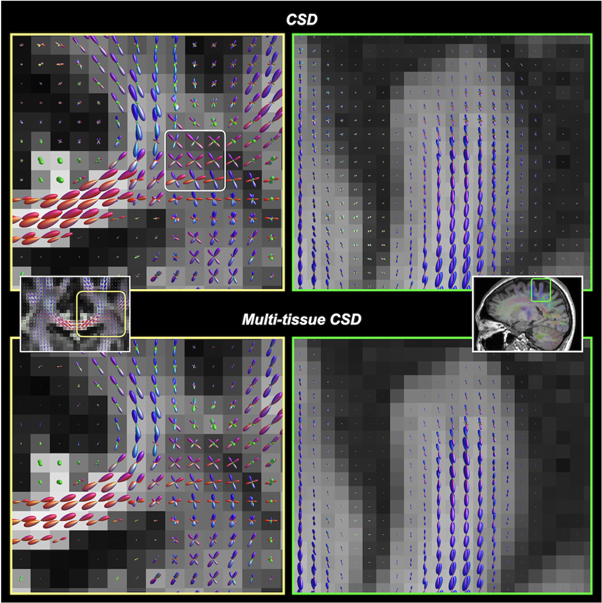

4.1.2. Methods for deriving fODF

Figure 7. Reconstruction of voxel-wise fODFs using CSD (upper row) and multi-tissue CSD (bottom row). Left column: the same slice location shown in figure 5 (where the tensor model results in incorrect fibre orientation estimates). Right column: fODFs near a cortical gyrus. Multi-tissue CSD (Jeurissen et al 2014) decomposes the signal contribution from different tissue types (GM, WM, and CSF), and which significantly reduces the partial volume contamination between tissues. The resultant WM fODFs from multi-tissue CSD are more accurate at tissue interfaces. Notably, ventricles should normally contain CSF voxels (i.e. no WM compartment), the multi-tissue CSD technique completely suppresses the spurious fODFs that occur with the (single-tissue) CSD. Such an improvement is advantageous to any ODF-based tractography algorithms.